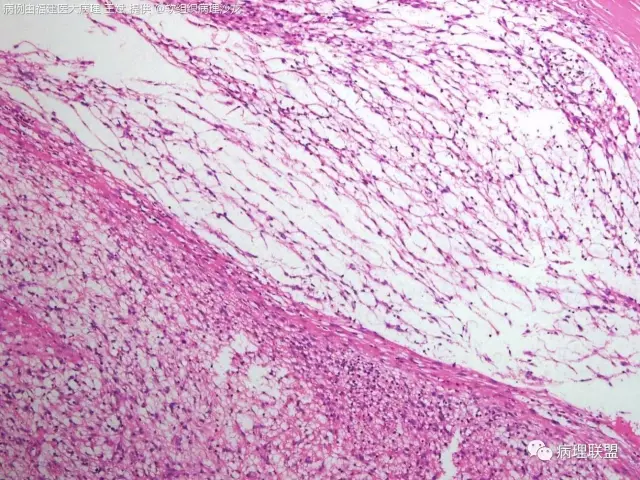

38岁,女性,手部小指背侧皮下肿物,3×2cm(病例由福建医大病理 王斌提供,致谢!)

是的,可以部分有粘液变,我见过的

血管瘤样纤维组织细胞瘤的肿瘤周围有淋巴细胞鞘,结节状分布,有假包膜,出血囊性变的为其主要特点,当然少数病例可以没有出血囊性变却出现粘液变。肿瘤细胞有一定异形性,属于低度恶性或交界性,最好做个FISH,看看有没有EWSR1-CREB1融合基因,刚查了一下,血管瘤样纤维组织细胞瘤还有另一种EWSR1-ATF1融合基因,无论是哪种,用EWSR1分离探针就可以检测